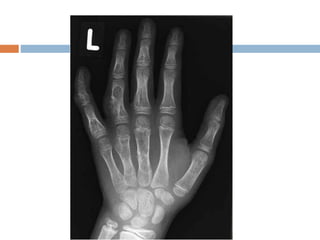

Chondroma

 Benign lesions of hyaling cartilage

 Common

 Affects all age groups

 Any bone can be involved but mainly affects

phalanges of the hands and feet

Diagnosis

 Radiography

 Benign appearing tumors

 Translucent

 Intralesional calcification– irregular

(stippled/punctate/popcorn)

 Small bones of hand hands and feet–

considerable erosion and expansion of the

overlying cortex

 Long bones– deep endosteal erosion (>2/3 of

the thickness of cortex) indicates a

chondrosarcoma

 Associated soft tissue mass– indicates